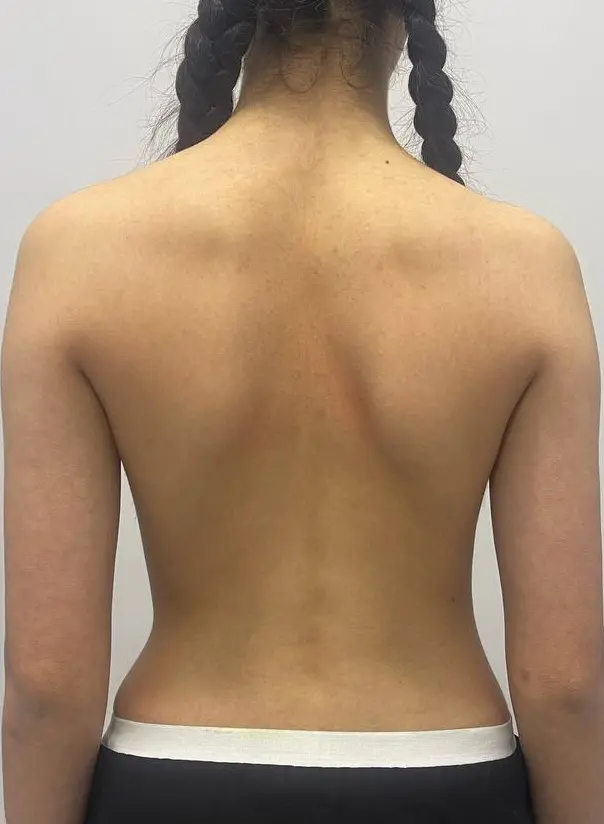

Нарушение осанки, асимметрия плечевого пояса и лопаток. После курса занятий оздоровительной гимнастикой — выравнивание осанки, улучшение мышечного баланса и контроля положения тела.

Нарушение осанки, асимметрия плечевого пояса и лопаток. После курса занятий — снижение асимметрии, улучшение мышечного баланса и устойчивости осанки.

До

После